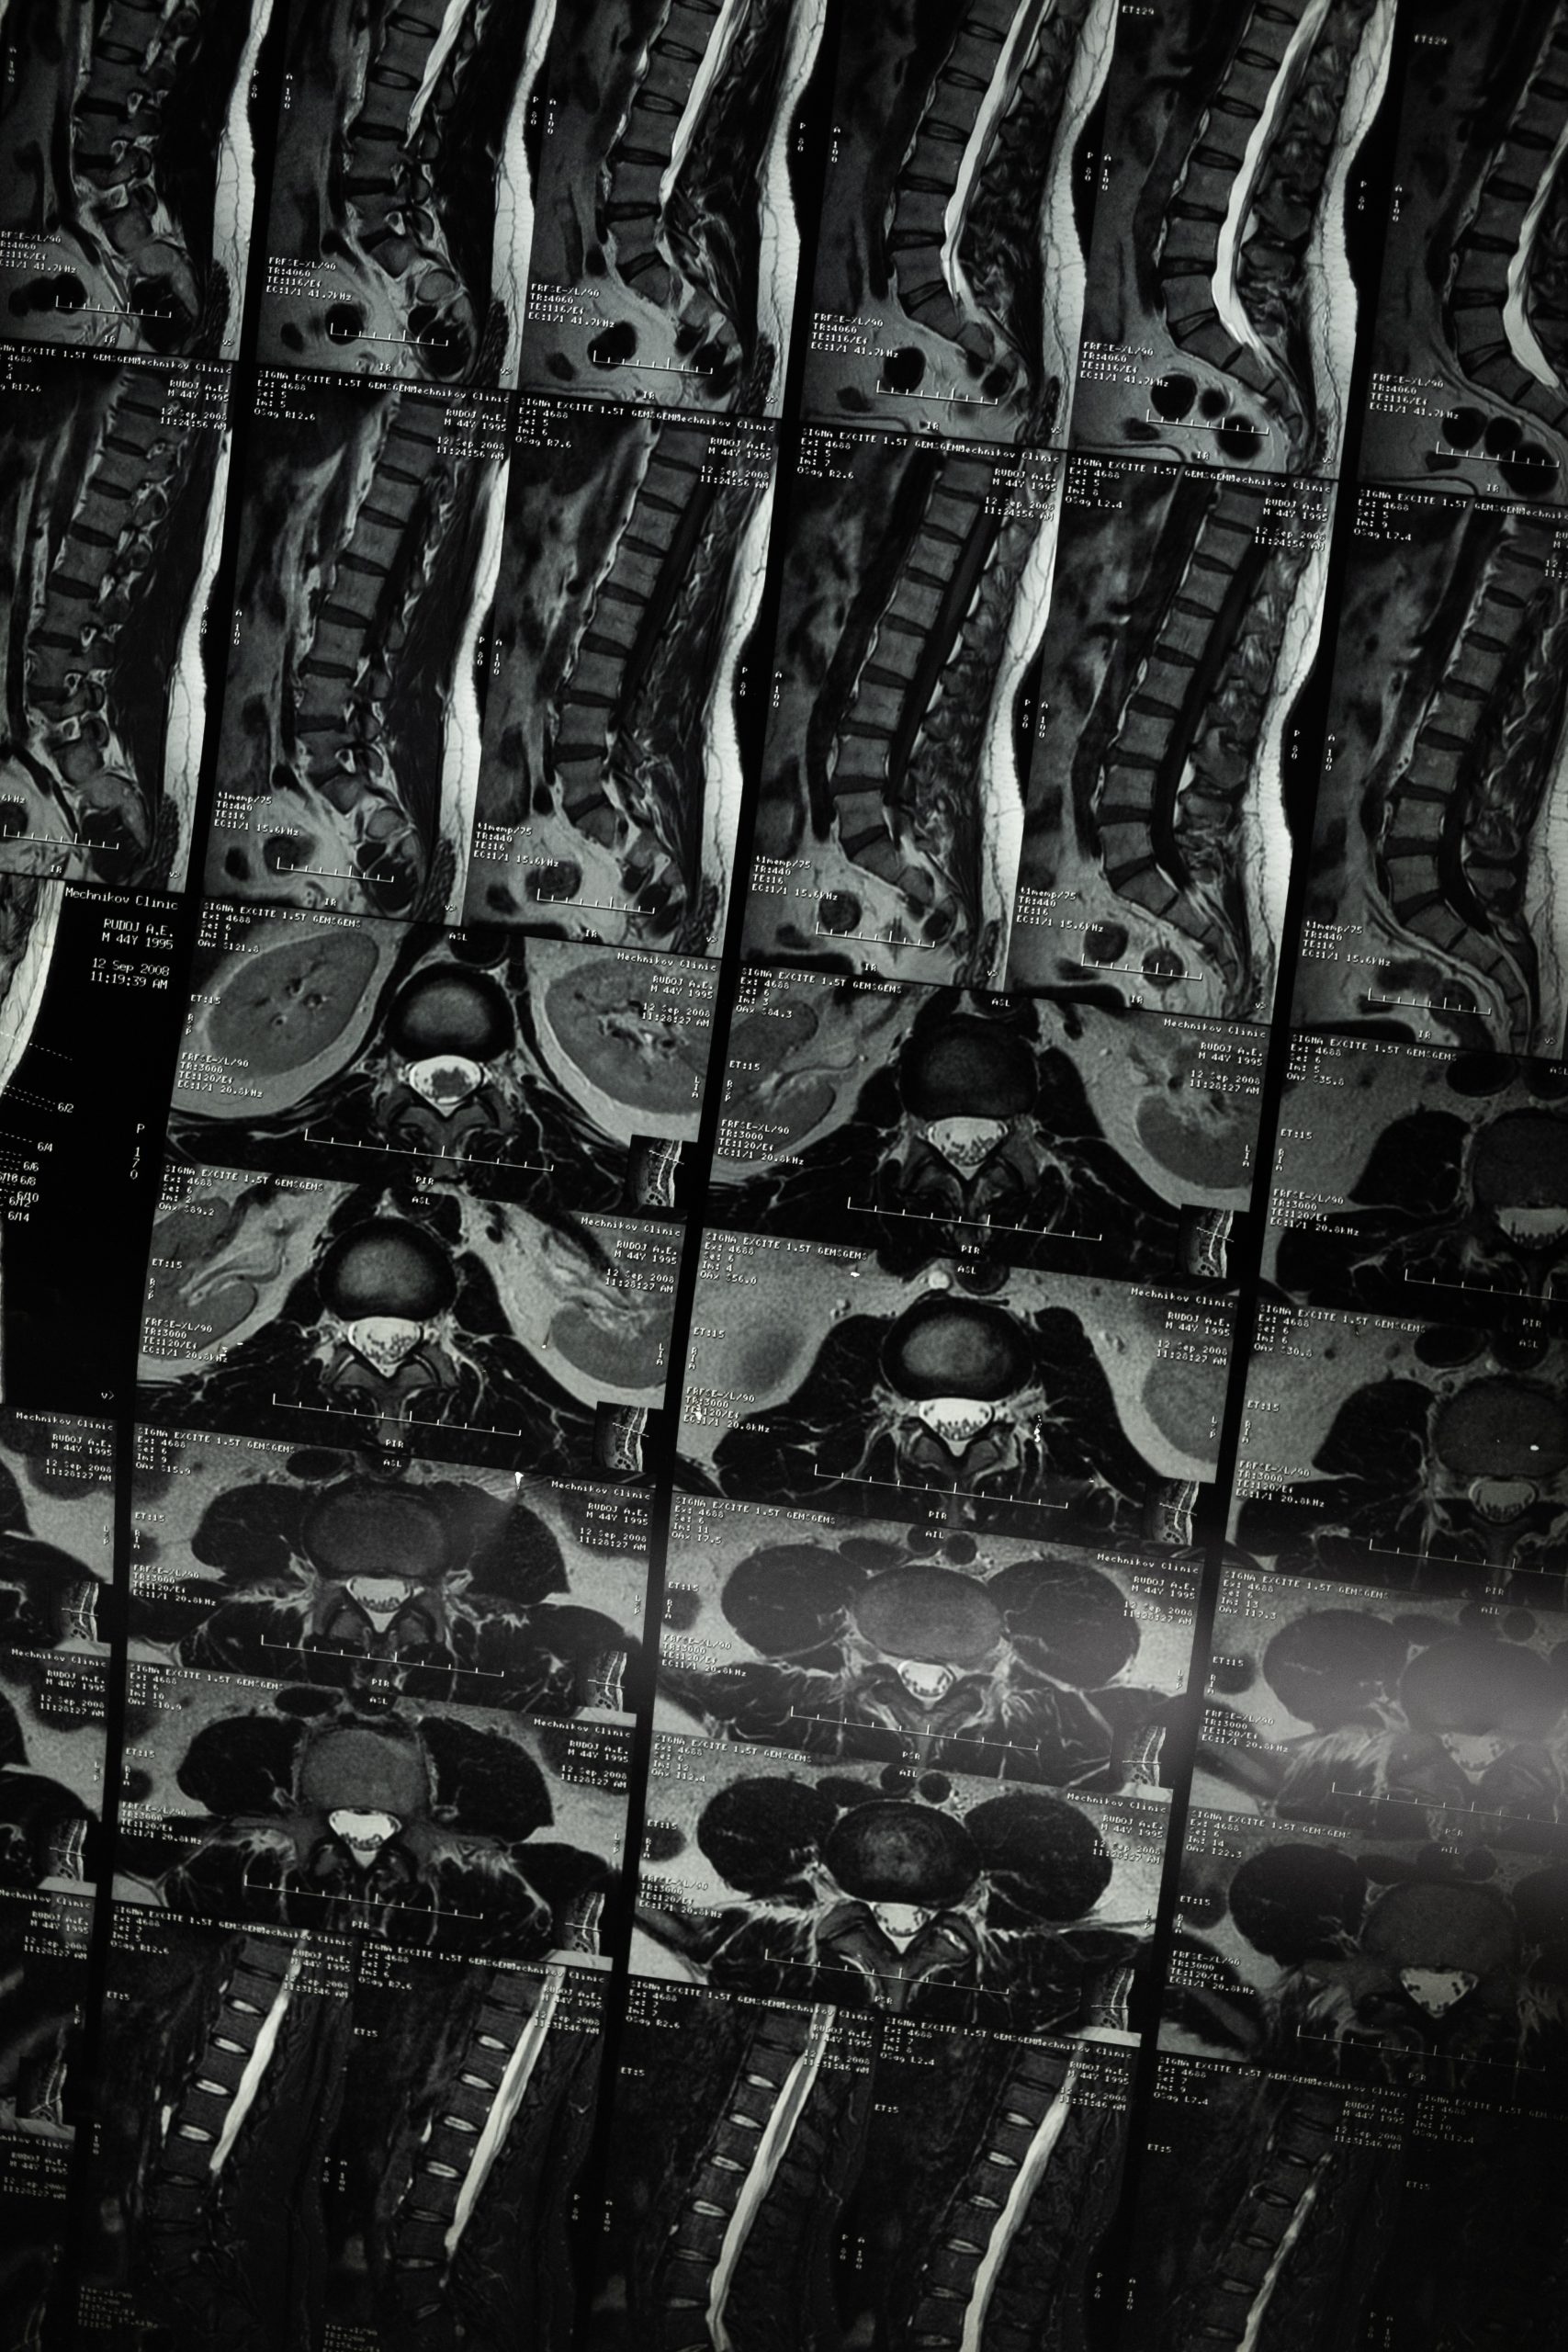

The majority of symptomatic disc herniations are found at the lower two lumbar interspaces, that is, about 50% at L4–5 and 47% at L5-S1 (1). The remaining 3% are found at higher lumbar levels (1). A r...